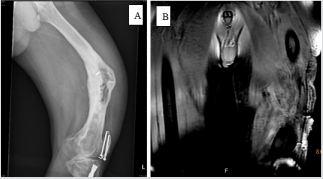

This 68-year-old male sustained trauma to the left leg in1990 with left femoral and tibia shaft fracture. He undergone osteosynthesis surgical intervention and received antibiotic treatment at that time. Unfortunately, left distal femur chronic osteomyelitis with sinus tract discharge developed (Figure 1). He received the surgery to remove implant, sequestrectomy, debridement, and local skin flap for many times. With newly developed palpable mass at anterolateral aspect of thigh and recurrent sinus tract discharge 7 years ago, he came to the out-patient department (OPD) for help. Physical exam revealed local tenderness, swelling, erythematous change, with small palpable mass over anterior thigh. Magnetic resonance imaging (MRI) (Figure 2) revealed that the abscess formation surrounded the distal femur and adjacent tissue, with infiltration of left thigh muscle. Repeat debridement and soft tissue tumor excision were performed. The histopathology report that left thigh mass was the soft tissue tumor with squamous epithelial hyperplasia with mild atypia. Ten months later, he noticed that the mass regrew and continued to increase in size, causing skin tenting and wound poor healing.

Figure 1: Anteroposterior X-ray

A. Presenting initial chronic osteomyelitis with femur varus deformity and lateral cortex erosion. MRI

B. Presenting left femur osteomyelitis with infectious status of muscle and abscess formation.